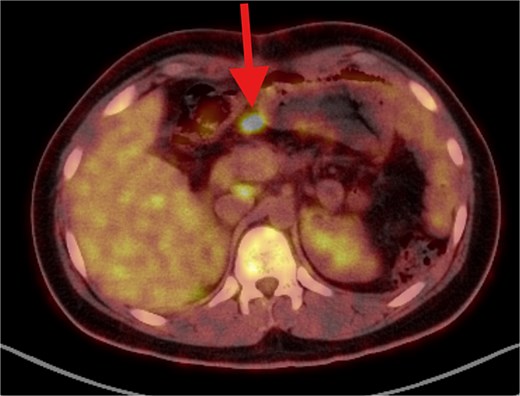

PET/CT scan showing a clear surgical bed. Almost complete metabolic resolution of the previous hypermetabolic abdominal deposits. Development of focal hypermetabolic activity just anterior and abutting the lower spleen pole, at the projection of splenic flexure of the descending colon, this lesion is nonspecific.